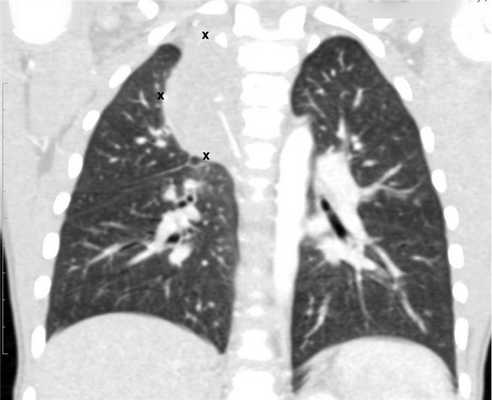

![Метастазы в легких до лечения и после 4х циклов химиотерапии по схеме «ВЕР» (КТ грудной клетки)]()

Метастазы в легких до лечения и после 4х циклов химиотерапии по схеме «ВЕР» (КТ грудной клетки)